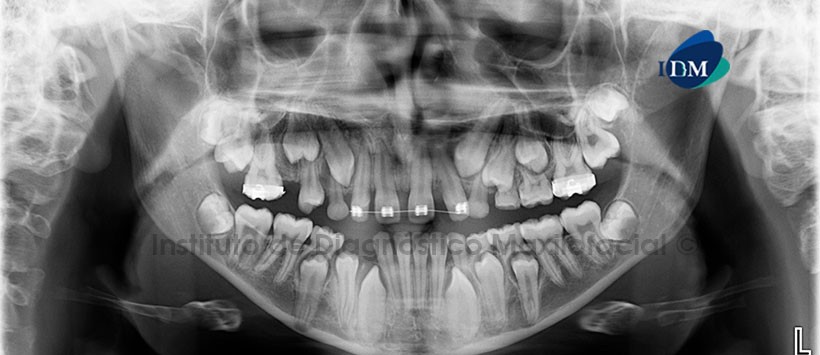

En la radiografía panorámica (Figura 1) se observa rarefacción a nivel de furcación de la pieza 47 que ocasiona la pérdida de lámina dura. Se aprecia además alteración en la morfología coronal de la pieza 1.8.